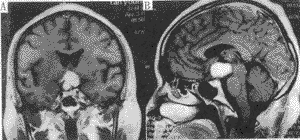

【摘要】 目的 探讨视交叉-下丘脑胶质瘤的近代诊治。方法 回顾性分析1983~1997年28例视交叉-下丘脑胶质瘤的临床表现,手术方法和疗效。结果 本组以头痛、视力障碍和内分泌改变为主要临床表现。MRI是主要的诊断方法。根据肿瘤主体部位选择手术入路。肿瘤全切除、次全切除和部分切除分别为8、12、8例。术后症状好转16例,7例出现下丘脑相关的症状群。严重下丘脑反应4例在术后1周内死亡。16例随访5个月至10年,平均3.5年,5例在2年内死亡,11例Karnofsky评分为50~60分。结论 视交叉-下丘脑胶质瘤的恶性程度与年龄有关。手术可切除肿瘤,明确诊断,恢复脑脊液循环。但是不强求全切,保存功能和减少对周围组织的损伤,是减少手术后并发症的关键,结合放疗和化疗,可使患者长期生存。

【Abstracts】Objective To investigate the status of diagnosisand treatment of optic chiasmatic-hypothalamic glioma (OCHG). Methods Aretrospective review of 28 cases with OCHG surgically treated between 1983-1997 wasconducted, focusing on their clinical features, surgical approaches and outcomes.Results Headache,vision disturbance and endocrine changes were main complaints.MRI was major diagnosticmodality. Unilateral subforntal, subfrontal trans-lamina terminalis and pterionalapproaches were applied for the tumors with main lesions in optic chiasma, transcallosaland transventricle approaches for main lesions in the third ventricle. Total, subtotal andpartial removal of tumors were achieved in 8, 12, 8 cases respectively. Symptoms and signswere improved in 16 cases. Seven cases showed hypothalamic-related signs. Four cases diedfrom severe hypothalamic reactions within one week after operations. Sixteen cases werefollowed up from 5 months to 10 years. Five cases died in two years after surgeries.Karnofsky scales of 11 patients were 50-60. Conclusions Malignany ofOCHG is related with age. Surgery is necessary for definire diagnosis and reestablishmentof CSF pathway, for the resection of exophytic and suprasellar tumors or the lesions inthe third ventricle. It is important for decreased complications to perform no intentionalradical surgery and lessen damage of surrounding tissues. The patients who got safeoperations and chemotherapy or radiotherapy will have longer time survival.